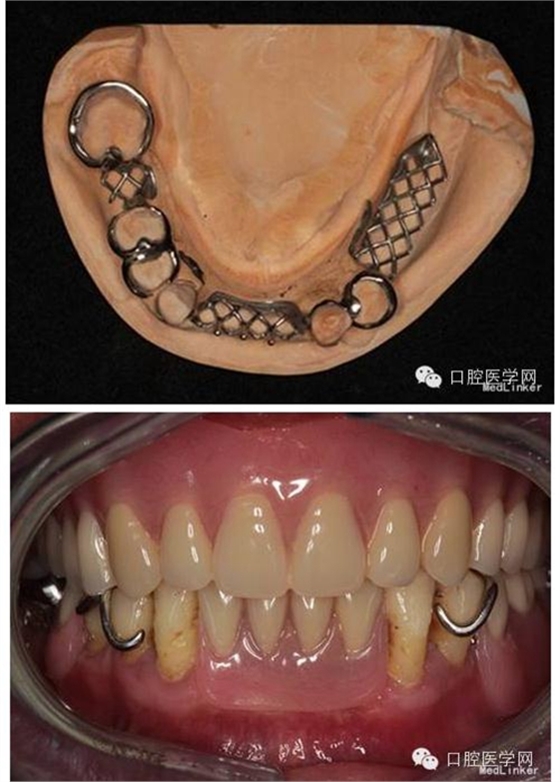

第2次就診:試個別托盤,磨改邊緣;上頜印模膏邊緣整塑;下頜處理預(yù)留牙,基牙預(yù)備;藻酸鹽取終印模,灌模;上頜制作暫基托,下頜制作鈷鉻合金支架。

第3次就診:試支架;試暫基托;制作蠟堤;記錄垂直距離、水平關(guān)系;轉(zhuǎn)移面弓;比色模型上he架,排牙。

第4次就診:試排牙,充膠第5次就診:初戴義齒,調(diào)he,醫(yī)囑。

本例患者通過系統(tǒng)的檢查發(fā)現(xiàn)#34頸部存在楔狀缺損,予Z350充填治療后再行修復(fù)。#33#43有一定程度的伸長約2mm,有可能會影響前伸he平衡,但患者強烈拒絕調(diào)磨牙齒,并且考慮到磨改頜面可能造成基牙敏感甚至必要時需行根管治療等增加治療時間及治療費用,告知患者情況后,患者無法接受,因此未對其進行調(diào)磨。人工牙排列時注意避讓開天然牙,可減小前牙覆he增加覆蓋,以利于獲得前伸he平衡。、